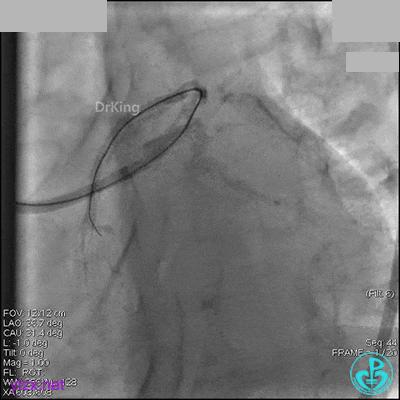

AL 1.0指引导管到位,简单短时尝试导丝不能顺利通过前降支或回旋支病变。改变策略处理右冠脉病变,计划植入2枚支架。AL指引导管到位,Sion blue导丝到达右冠脉远端。导丝通过后1.5mm及2.5mm球囊14~16atm充分扩张中段病变。

右冠脉中段充分扩张后欲植入3.5×38mm支架时,支架难以通过中远段扭曲处,且指引导管、导丝弹出飞扬。反复尝试导丝重新到达右冠脉远端时通过不顺利,局部造影剂滞留,远端血流接近3级。